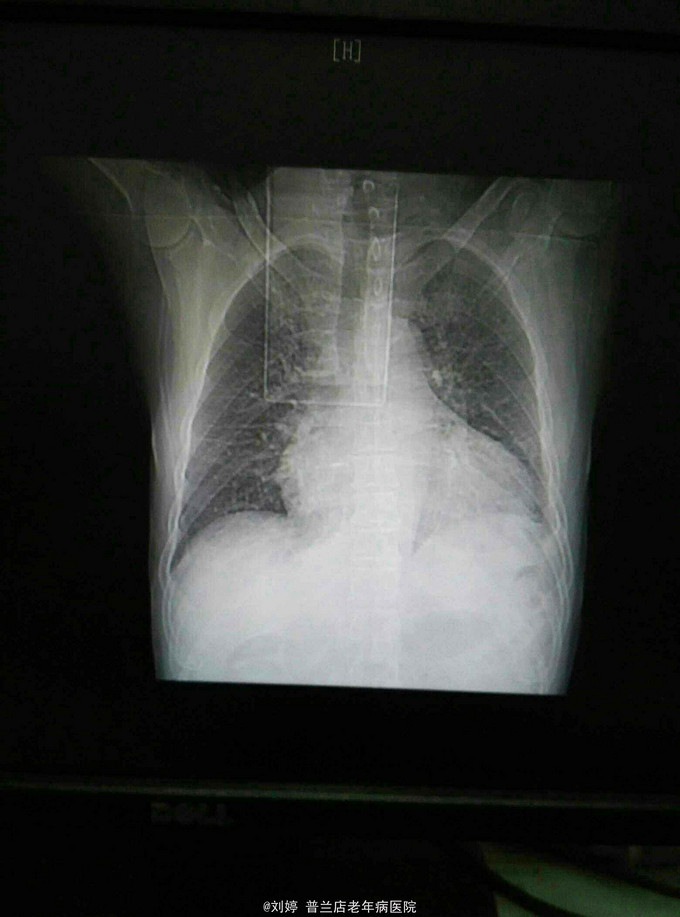

T 37.5 P 96 R 22 BP 180/120 神清,语明,双肺呼吸音粗,双肺底呼吸音消失,局部可闻及湿罗音,心界扩大,心音低顿,心率96次每分,律齐,腹软,无压痛,肝脾未及,双下肢重度凹陷性浮肿,双手足皮温低,痛温觉减退,双足背动脉 搏动减弱,左足第三趾发黑,局部脓性分泌物。四肢肌力减退,左侧肌力四级,右侧上肢肌力三级,右侧下肢二级,膝腱反射减弱。双巴氏征阴性。随机指间血糖5.6mmol/l,心电图:窦性心律,96次/分,二,三,AVF异常Q波。胸片,心脏增大,心包少量积液,双侧胸腔积液。血常规:WBC:15.75*109/L,中性粒细胞百分比78.5,血离子:钾 3.43 尿常规:蛋白3+,葡萄糖2+,隐血1+.科内三合一正常,血BNP大于10000,D二聚体正常。

冠心病 心功能四级 左心衰 胸腔积液 糖尿病 糖尿病周围神经病变 糖尿病视网膜病变 糖尿病肾病 高血压病3级极高危 脑梗死给予半卧位,吸氧,抗感染,利尿,减轻心脏负荷,改善循环,降压,调整血糖,纠正水电解质紊乱及对症治疗,住院14天,心衰好转,感染持续不能好转,二联左氧加四代头孢已上,血离子正常,突发应激性溃疡,意识模糊不清,转上级医院。